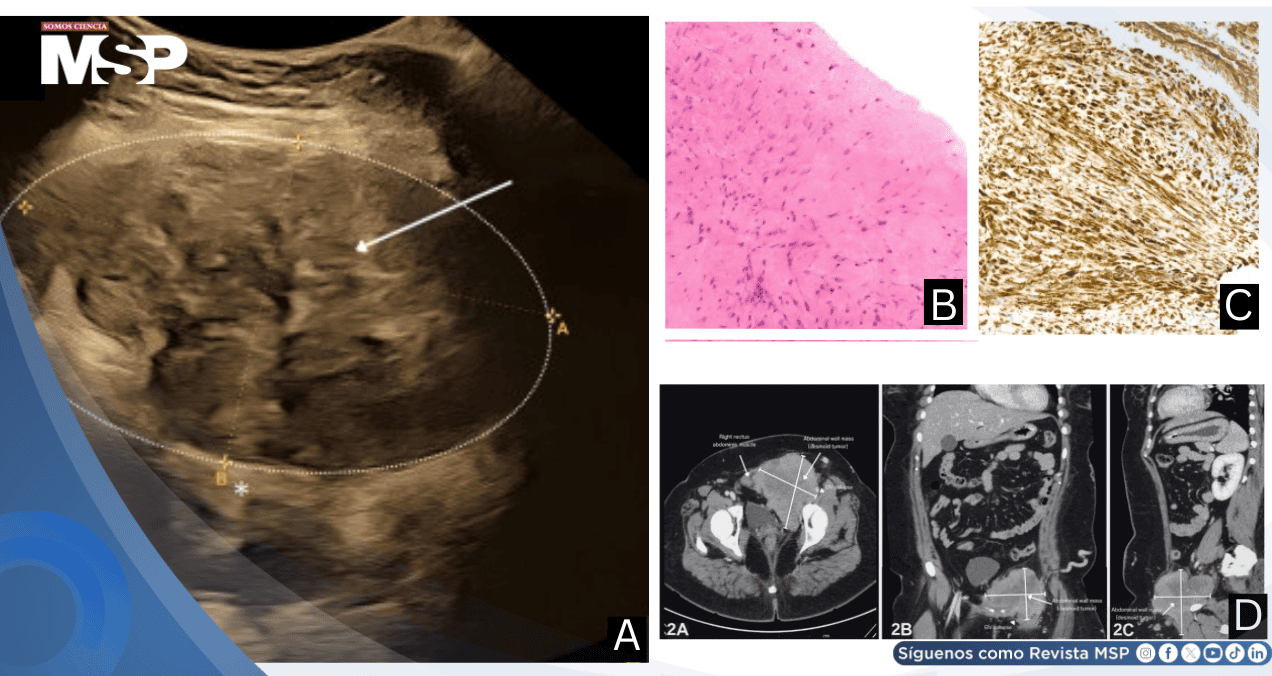

La evaluación exhaustiva en el período posparto incluyó tomografía computarizada de abdomen completo con contraste endovenoso, que documentó un incremento del tamaño tumoral a 10.1 por 10 por 9.5 centímetros.

Las imágenes demostraron una masa heterogénea en la pared abdominal inferior izquierda con compromiso bilateral de los músculos rectos abdominales, extensión al músculo psoas izquierdo, obturador interno y pectíneo, con infiltración hacia el canal inguinal.

Significativamente, se confirmó invasión de la vena ilíaca externa izquierda y la vena femoral común, además de identificarse un ganglio linfático inguinal ipsilateral levemente aumentado de tamaño.